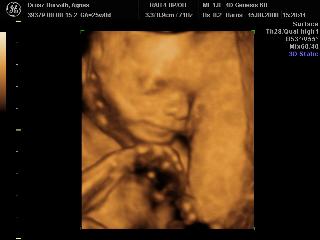

Pannaanya: tök jók a 4D-s képek! Siófok-Sóstó? Na az tőlünk kb. 7 km, ha olvasod és van kedved, akár össze is futhatnánk